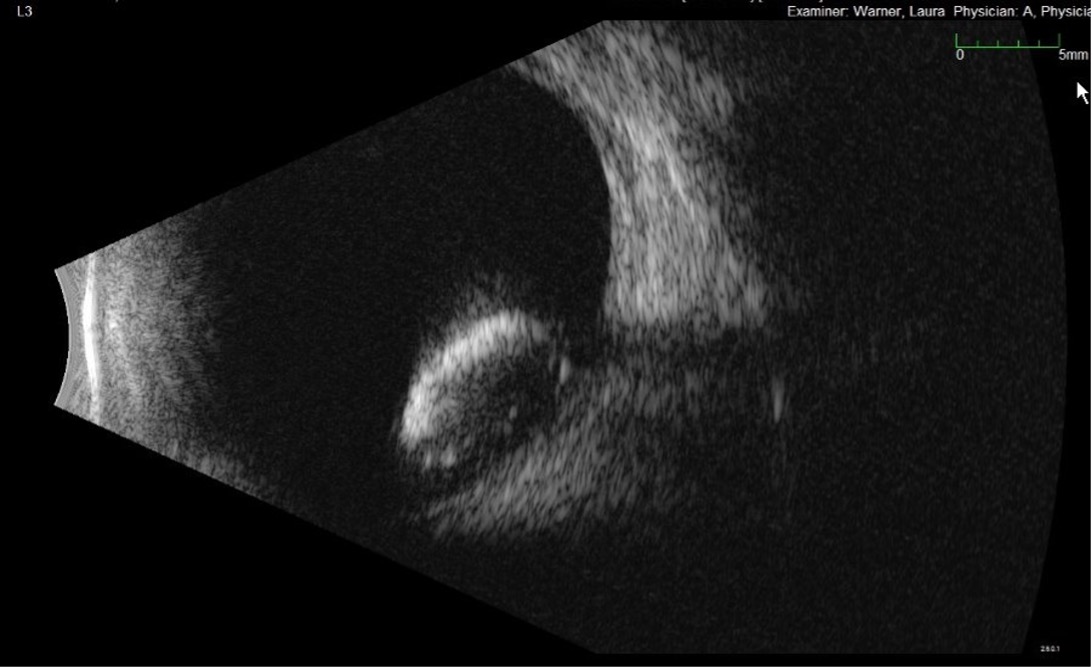

• B-scan ocular ultrasound was obtained in the left eye on initial presentation; findings are presented in Figures 2a, 2b (photos) and Figure 3 (video).

Figure 2a,2b. This is a formal B-scan oriented at L3 (2a, top) and T6E (2b, bottom), which shows the dense cataractous dislocated lens has fallen to the back and is resting on the retina. Notice the completely intact lens capsule.

Figure 3. A hyperechoic, biconvex mass is identified in the posterior chamber using B-scan ocular ultrasound.